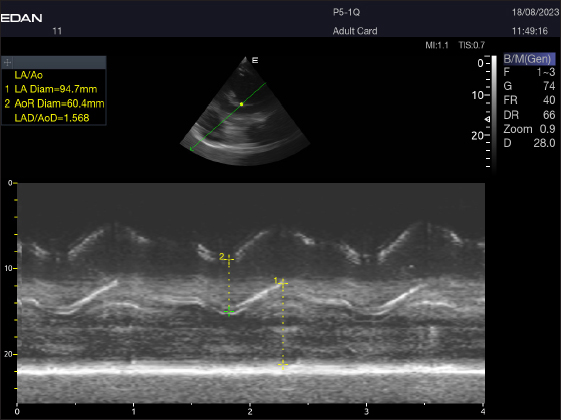

By positioning the probe perpendicularly in the fourth intercostal space or longitudinally in the fifth space with a little clockwise rotation, the interventricular septum, ventricles, and atria could be observed in the caudal long-axis four-chamber view (Fig. 1). From this vantage point, all camels could be seen to have a left ventricle, mitral valve, interventricular septum, right ventricle, and tricuspid valve. Figure 2 shows that in the short-axis image of the cardiac ventricles obtained with a little clockwise rotation at the 4th ICS, only the right ventricle, interventricular septum, and left ventricle were visible. Here, the dimensions of all camel heart were measured in M mode. The right parasternal two-dimensional short-axis pictures of the heart’s base in the first frame were used to determine the LA/Ao ratio, by applying 2D and M mode (Figs. 3 and 4). Despite some difficulties, we successfully acquired a pulmonary image by attempting to acquire the right ventricular outflow tract for the right short axis at the level of the great vessels.

Fig. 4. LA/Ao ratios for the right parasternal short axis of 18 racing camels at the great vessel level. Through the anatomical M mode.